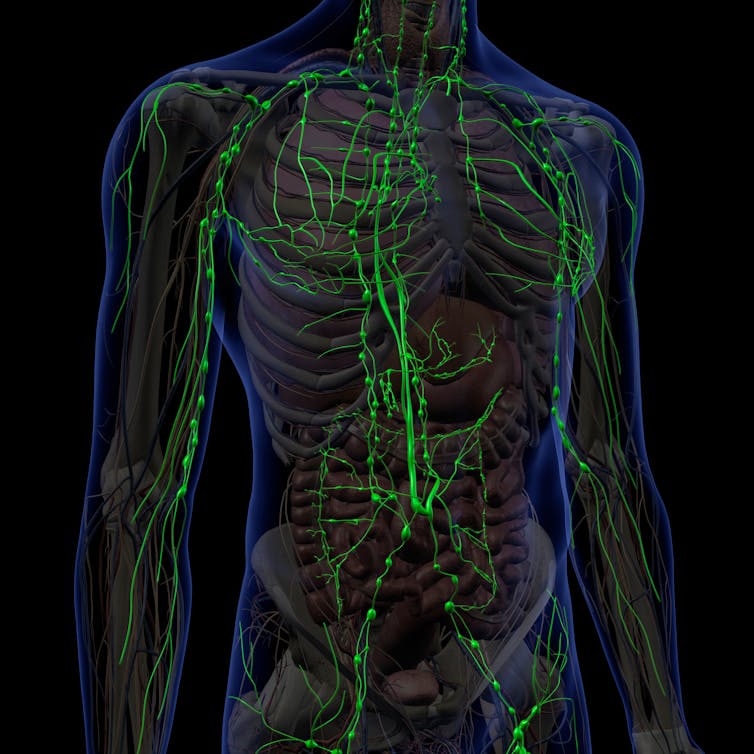

The lymphatic system has long been considered mysterious.

Unlike blood vessels, lymphatic vessels are not very visible to the naked eye, even during surgery. Because of this, the anatomy and functions of the lymphatic system have historically not been well studied. The fluid in the lymphatic system was named “lymph” after the Greek nymph – a mythical creature associated with clear streams – and the Roman Lympha, goddesses of fresh water.

But the lymphatic system – and the lymph nodes within it – plays fascinating and important roles in health and disease, from fighting off infection to maintain the body’s fluid balance.

The lymphatic system protects the body against foreign invaders and enables us to mount an immune response.

Lymphocytes are mostly contained in about 700 peanut-sized lymph glands in the body. Enlarged lymph nodes, such as after a vaccination or with an infection, are due to lymphocytes mounting a protective immune response. Lymphoma is a cancer that happens when lymphocytes multiply uncontrollably and cause swollen lymph glands throughout the body.

Some lymphocytes travel around the body conducting pathogen surveillance for invading bugs. They circulate between lymph nodes, lymph and the blood.

Starting in the tissues just under the skin and around our organs, the lymphatic system is a one-way circulatory system. Lymphatic vessels carry lymph from the tissues via lymph nodes and then into veins that drain directly into the heart.